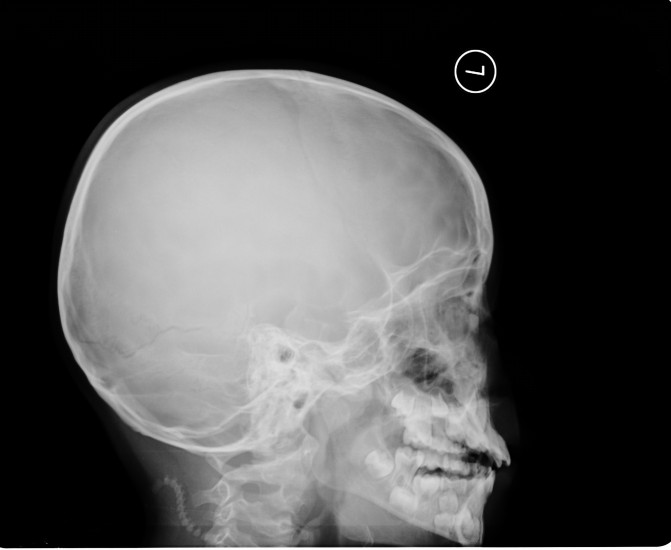

标题: x4344:男,9岁。好久不见的东西了。左枕部外伤一周。 [打印本页]

标题: x4344:男,9岁。好久不见的东西了。左枕部外伤一周。

侧位不标准,左侧人字缝增宽,有外伤史吗?其他无明显异常。

左侧枕乳缝增宽,提示颅缝分离型骨折。

都愿往复杂方面想,很简单,左枕部线形骨折,我仅这么认为。

支持左枕部线形骨折。

枕骨骨折、左侧顶乳缝分离。

支持 左侧颞枕部颅骨线形骨折。建议:ct扫描检查了解颅内情况。